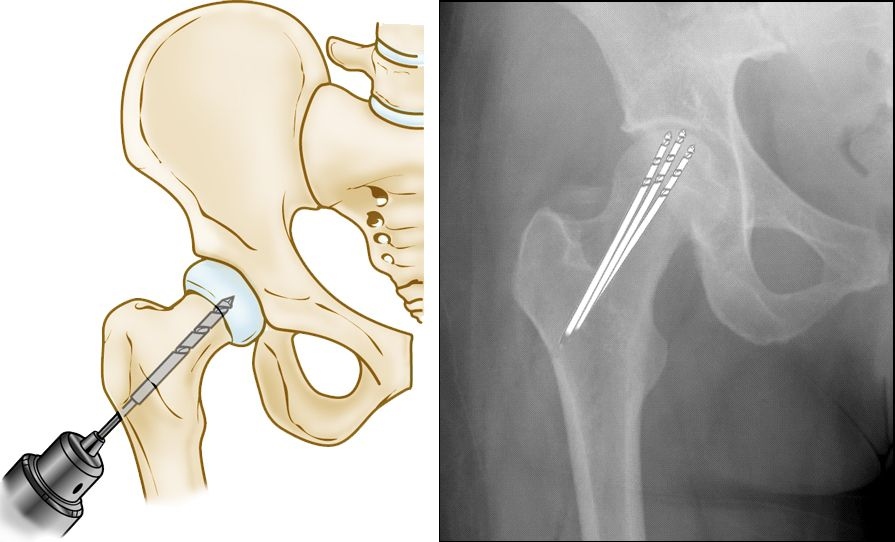

درمان جراحی

در موارد پیشرفته، جراحی ضروری است:

• کاهش فشار مرکزی: ایجاد سوراخ برای بهبود خون‌رسانی.